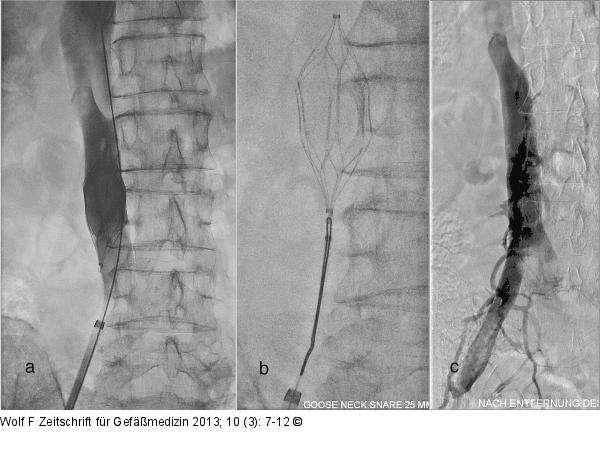

Abbildung 3a-c: Vena-cava-Filter (a): Cavographie vor Filterentfernung, es finden sich hier keine relevanten Thromben im Bereich des Filters; (b): Die Fass-Schlinge ist bereits um das Häkchen des Cordis Optease® Vena-cava-Filters gelegt und zugezogen; (c): Cavographie nach Filterentfernung. |

(a): Cavographie vor Filterentfernung, es finden sich hier keine relevanten Thromben im Bereich des Filters; (b): Die Fass-Schlinge ist bereits um das Häkchen des Cordis Optease® Vena-cava-Filters gelegt und zugezogen; (c): Cavographie nach Filterentfernung. |